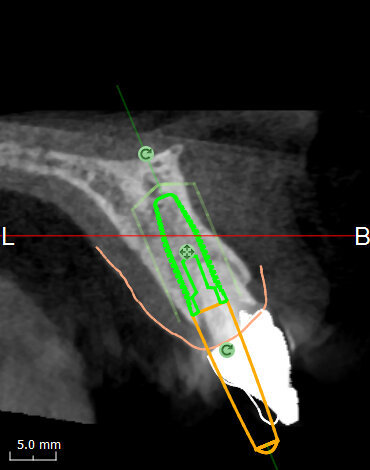

Analysing the CBCT scan

It became evident that the short-rooted tooth could be extracted without compromising the buccal bone, and that there was sufficient bone volume and quality to obtain good primary stability of the implant. Thanks to the AIS 3D App software, this information can be visualised using the bone density tool and linear measures tool (Fig. 10c) and represented in a graphic or according to a coloured scale. The presence of the nasopalatine duct prohibited ideal palatal positioning of the implant, and if the implant were to be placed flush with the palatal alveolar bone, this would have resulted in a 1.5–2.0 mm high exposure of the implant collar on the buccal aspect (Fig. 11b). This information, combined with the aesthetic analysis, led to the decision to place the implant in that position and to augment the buccal bone volume with a contemporaneous GBR procedure, thus also providing for major soft tissue support. As often described in the literature, it is to be expected that in some measure the implant will deviate buccally2–4 from the original planning because of the major mechanical resistance of the palatal plate. The author’s team prefers whenever possible screw-retained solutions. Several production centres are capable of milling angulated screw access holes in cobalt-chromium abutments of up to 25°,5 which is a range that covers most cases in daily practice. It can be easily checked in the implant planning software whether the future access hole will exit on the palatal aspect of the tooth, either by angulating the implant extension tool or by choosing a virtual abutment from the library. Confirming being in the safety range from this point of view allowed for an approach that foresaw the implant in native bone without the necessity for major GBR on the apical aspect of the implant. Knowing that a flap needed to be raised to facilitate the marginal tissue augmentation, it was decided to use a surgical guide (Figs. 11c) for only the first drill to determine with precision the position and angulation of the osteotomy that would be performed freehand thereafter. In order to limit surgery time and eliminate unpredictable factors inherent in immediate loading, a removable temporary prosthetic tooth was produced in advance.